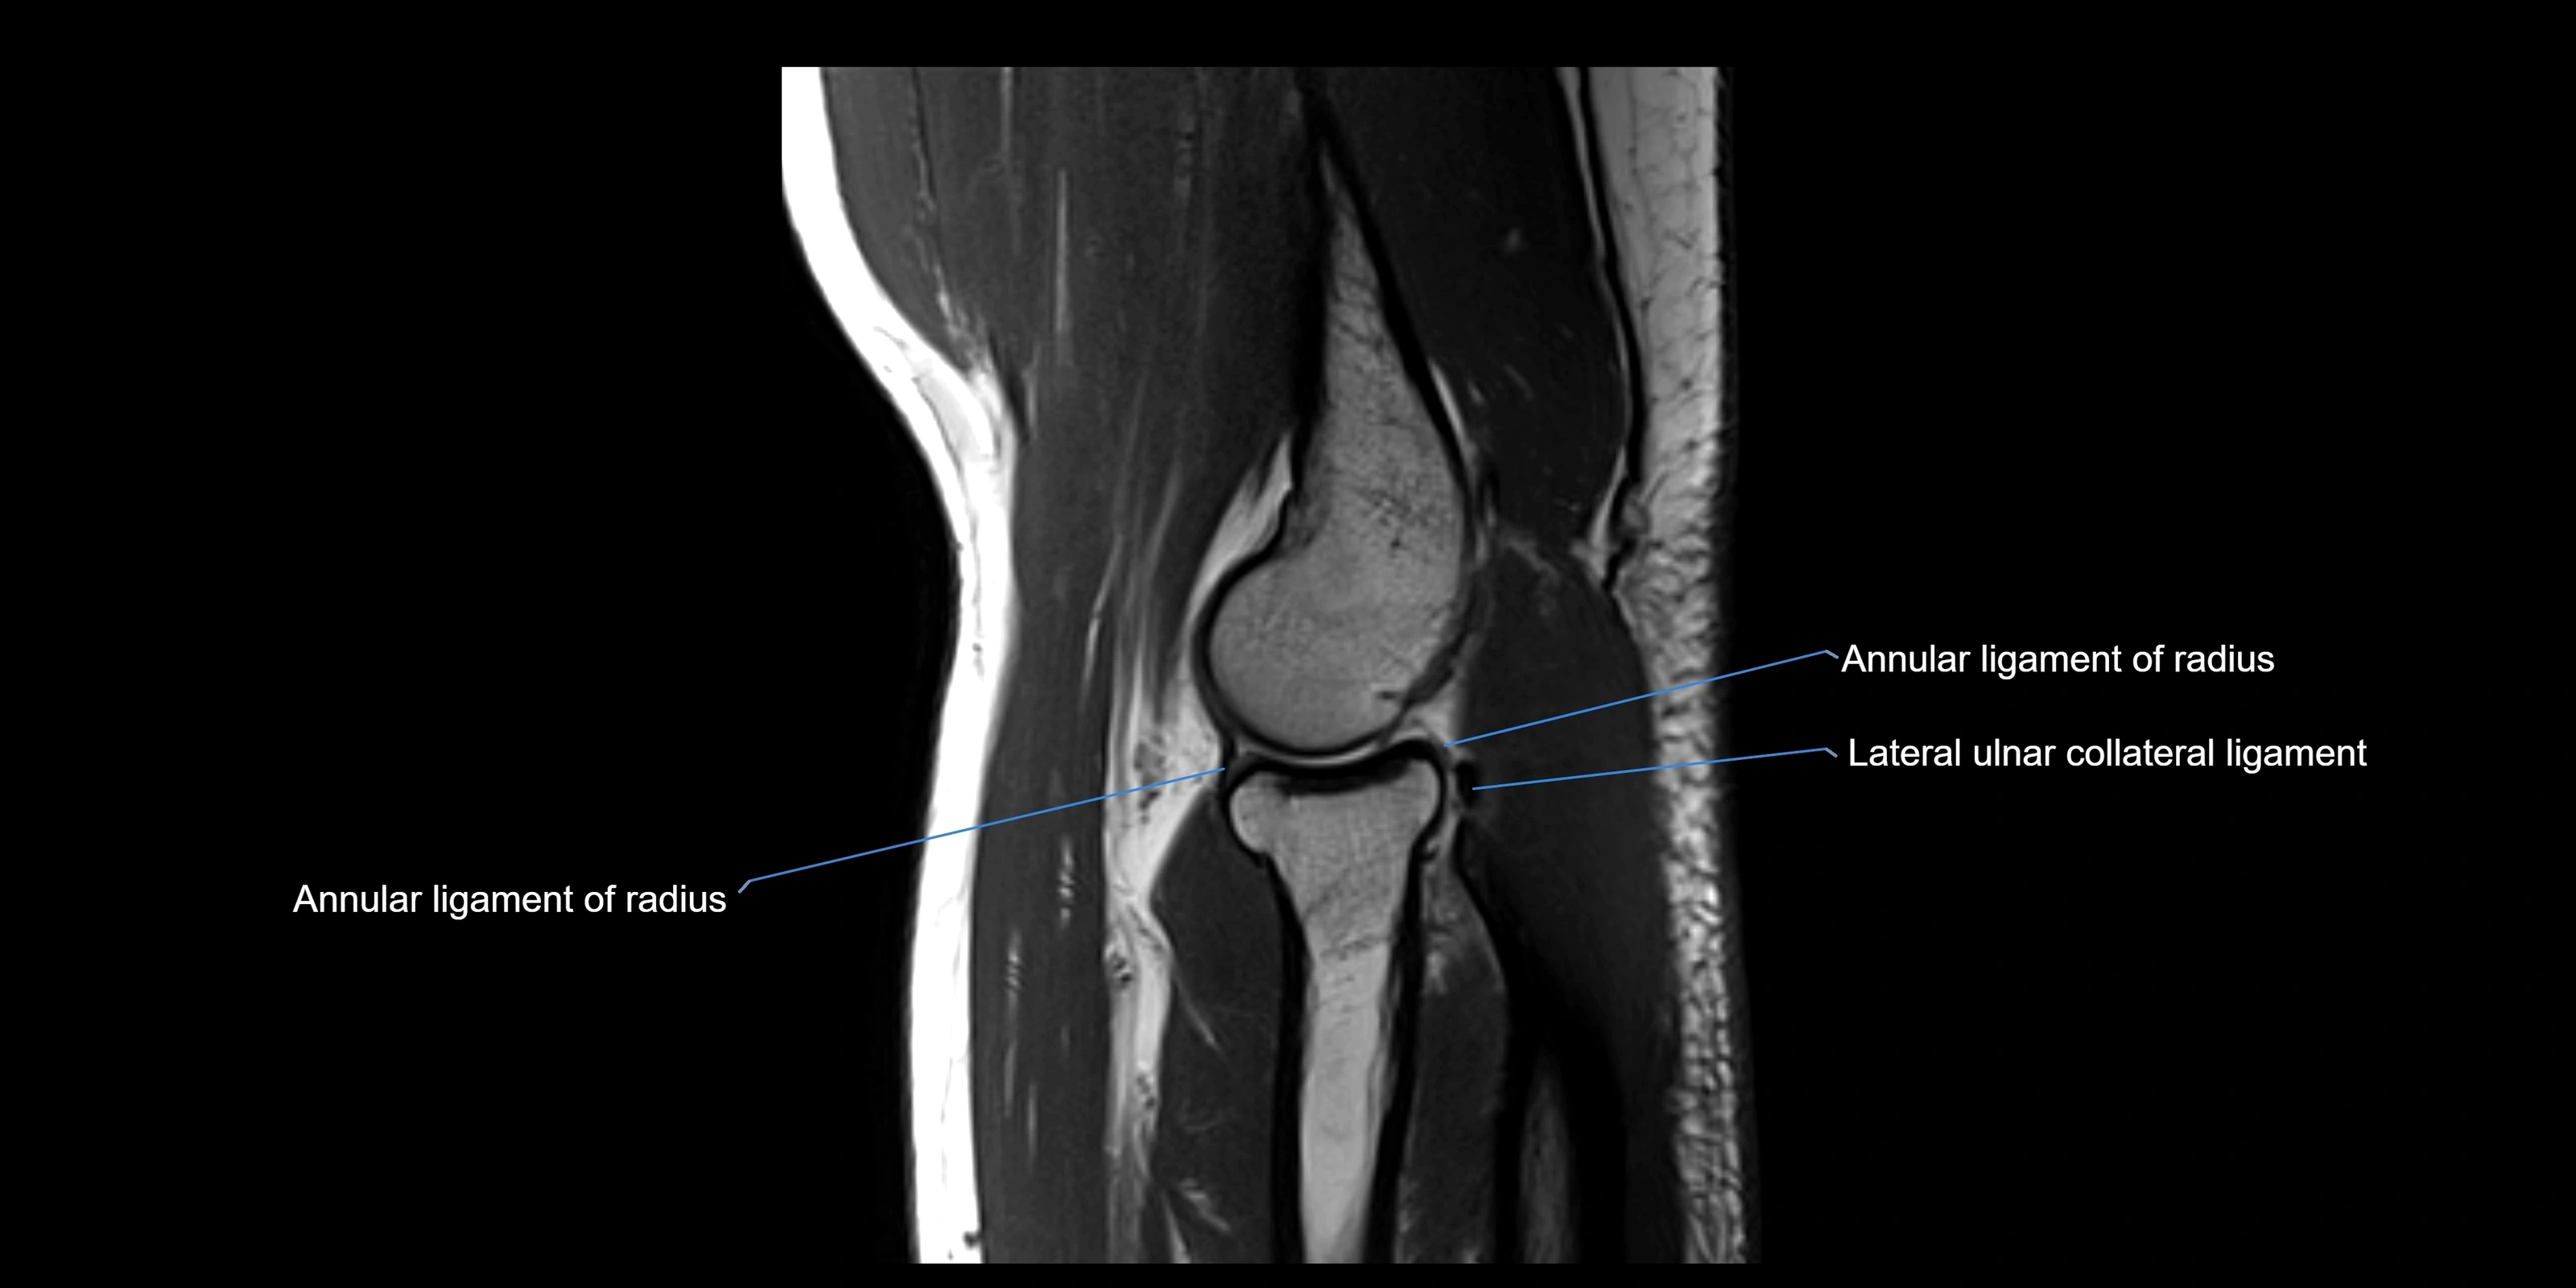

The annular ligament of the radius is a strong, circular band of fibers that encircles the head and neck of the radius, holding it securely against the radial notch of the ulna. It forms part of the proximal radioulnar joint, permitting smooth rotation of the radius during pronation and supination of the forearm.

The ligament acts like a collar or loop, maintaining radial head stability while allowing rotation. It is essential for forearm motion, elbow stability, and load transmission from the radius to the ulna and humerus.

Origin, Course, and Insertion

• Origin: Arises from the anterior margin of the radial notch of the ulna.

• Course: Forms a strong circular band that wraps around the radial head and neck, maintaining them within the radial notch.

• Insertion: Attaches to the posterior margin of the radial notch, completing a fibrous ring around the radial head.

• The inner surface of the ligament is lined with synovial membrane, allowing frictionless rotation.

MRI Appearance

T1-weighted images:

• Ligament: low signal intensity (dark), appearing as a continuous band around the radial head.

• Adjacent fat and marrow: bright, creating contrast with the ligament.

• Thickening or disruption indicates injury or fibrosis.

• Joint capsule and synovium seen as thin low-signal lines contiguous with ligament margins.

MRI Arthrogram Appearance

• Contrast outlines the proximal radioulnar joint and radial head recess.

• Normal ligament appears as a dark ring surrounding the radial head, containing the injected contrast within the joint cavity.

• Partial tear: contrast extends along the ligament or beneath its fibers.

• Complete tear or subluxation: contrast extravasates around the radial head or ulna, indicating discontinuity.

• Detects capsular defects, instability, or synovial invagination with high sensitivity.